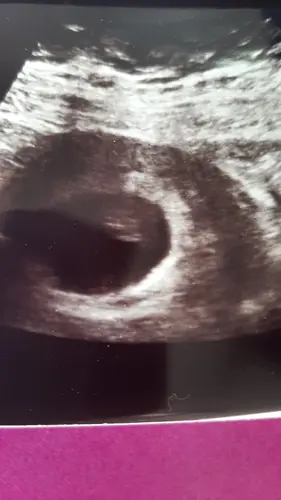

Ik had bij mijn eerste zwangerschap de eerste inwendige echo. Ze bleef maar zoeken en 'rare' vragen stellen ' had je echt wel een positieve test, ben je echt niet ongesteld geworden etc'. Ze zag niks..

Toch nog voor de zekerheid uitwendig en boem: kloppend hartje, alles.

Ik bleek een cyste te hebben, ze hebben dus inwendig een echo van mijn cyste gemaakt waardoor ze niks zagen.

De 2 zwangerschappen erna nooit meer een inwendige echo toegelaten.

Je mag zeker een uitwendige echo eisen he, voor nu en in de toekomst 馃┓